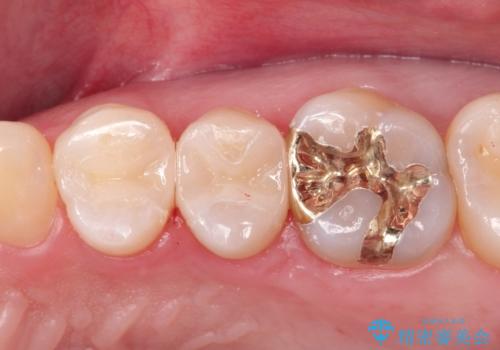

古い材料を除去すると中で虫歯が進行していたため、顕微鏡下で虫歯を除去した後セラミックインレー、PGAインレーにて修復治療を行いました。

PGA(ゴールド)クラウン、インレーの注意事項(リスク・副作用など)

- インレーおよびクラウンは脱離するリスクがあります

- 形成量はセラミックより少ないですが、歯の形成、修復後に歯に症状が出ることがあります